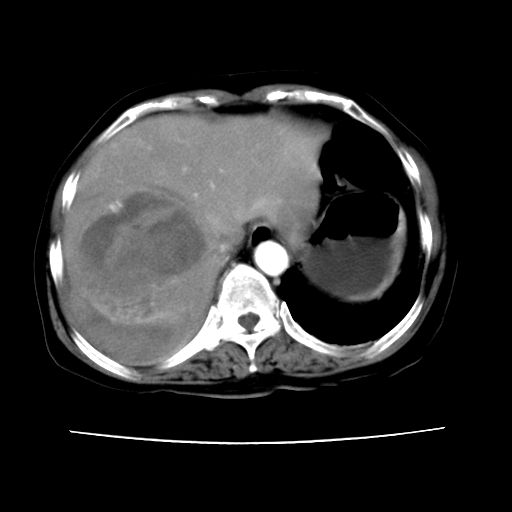

ct增强

考虑肝腺瘤出血可能,肝血管瘤增强表现不是很典型,放在第二。

6月份ct片显示肝内巨大混杂密度团块,伴包膜下积液(内含液液平面),增强多无明显强化。只能考虑肝占位病变,并肝内、血膜下血肿。肝ca并出血多见,而肝血管瘤并破裂出血少见。

从平扫+增强及治疗后复查片,病变明显缩小,不考虑肝癌出血可能,还是考虑为良性病变可能性大;单纯血肿并包膜下积液吧,病变强化没法解释,肝血管破裂出血吧,增强不符合典型血管瘤的表现,良性肿瘤破裂出血吧,复查片看来好像也不太支持(没做强化也不太好说)。本人还是考虑单纯肝内血肿并包膜下积液,强化是不是血管有外渗。